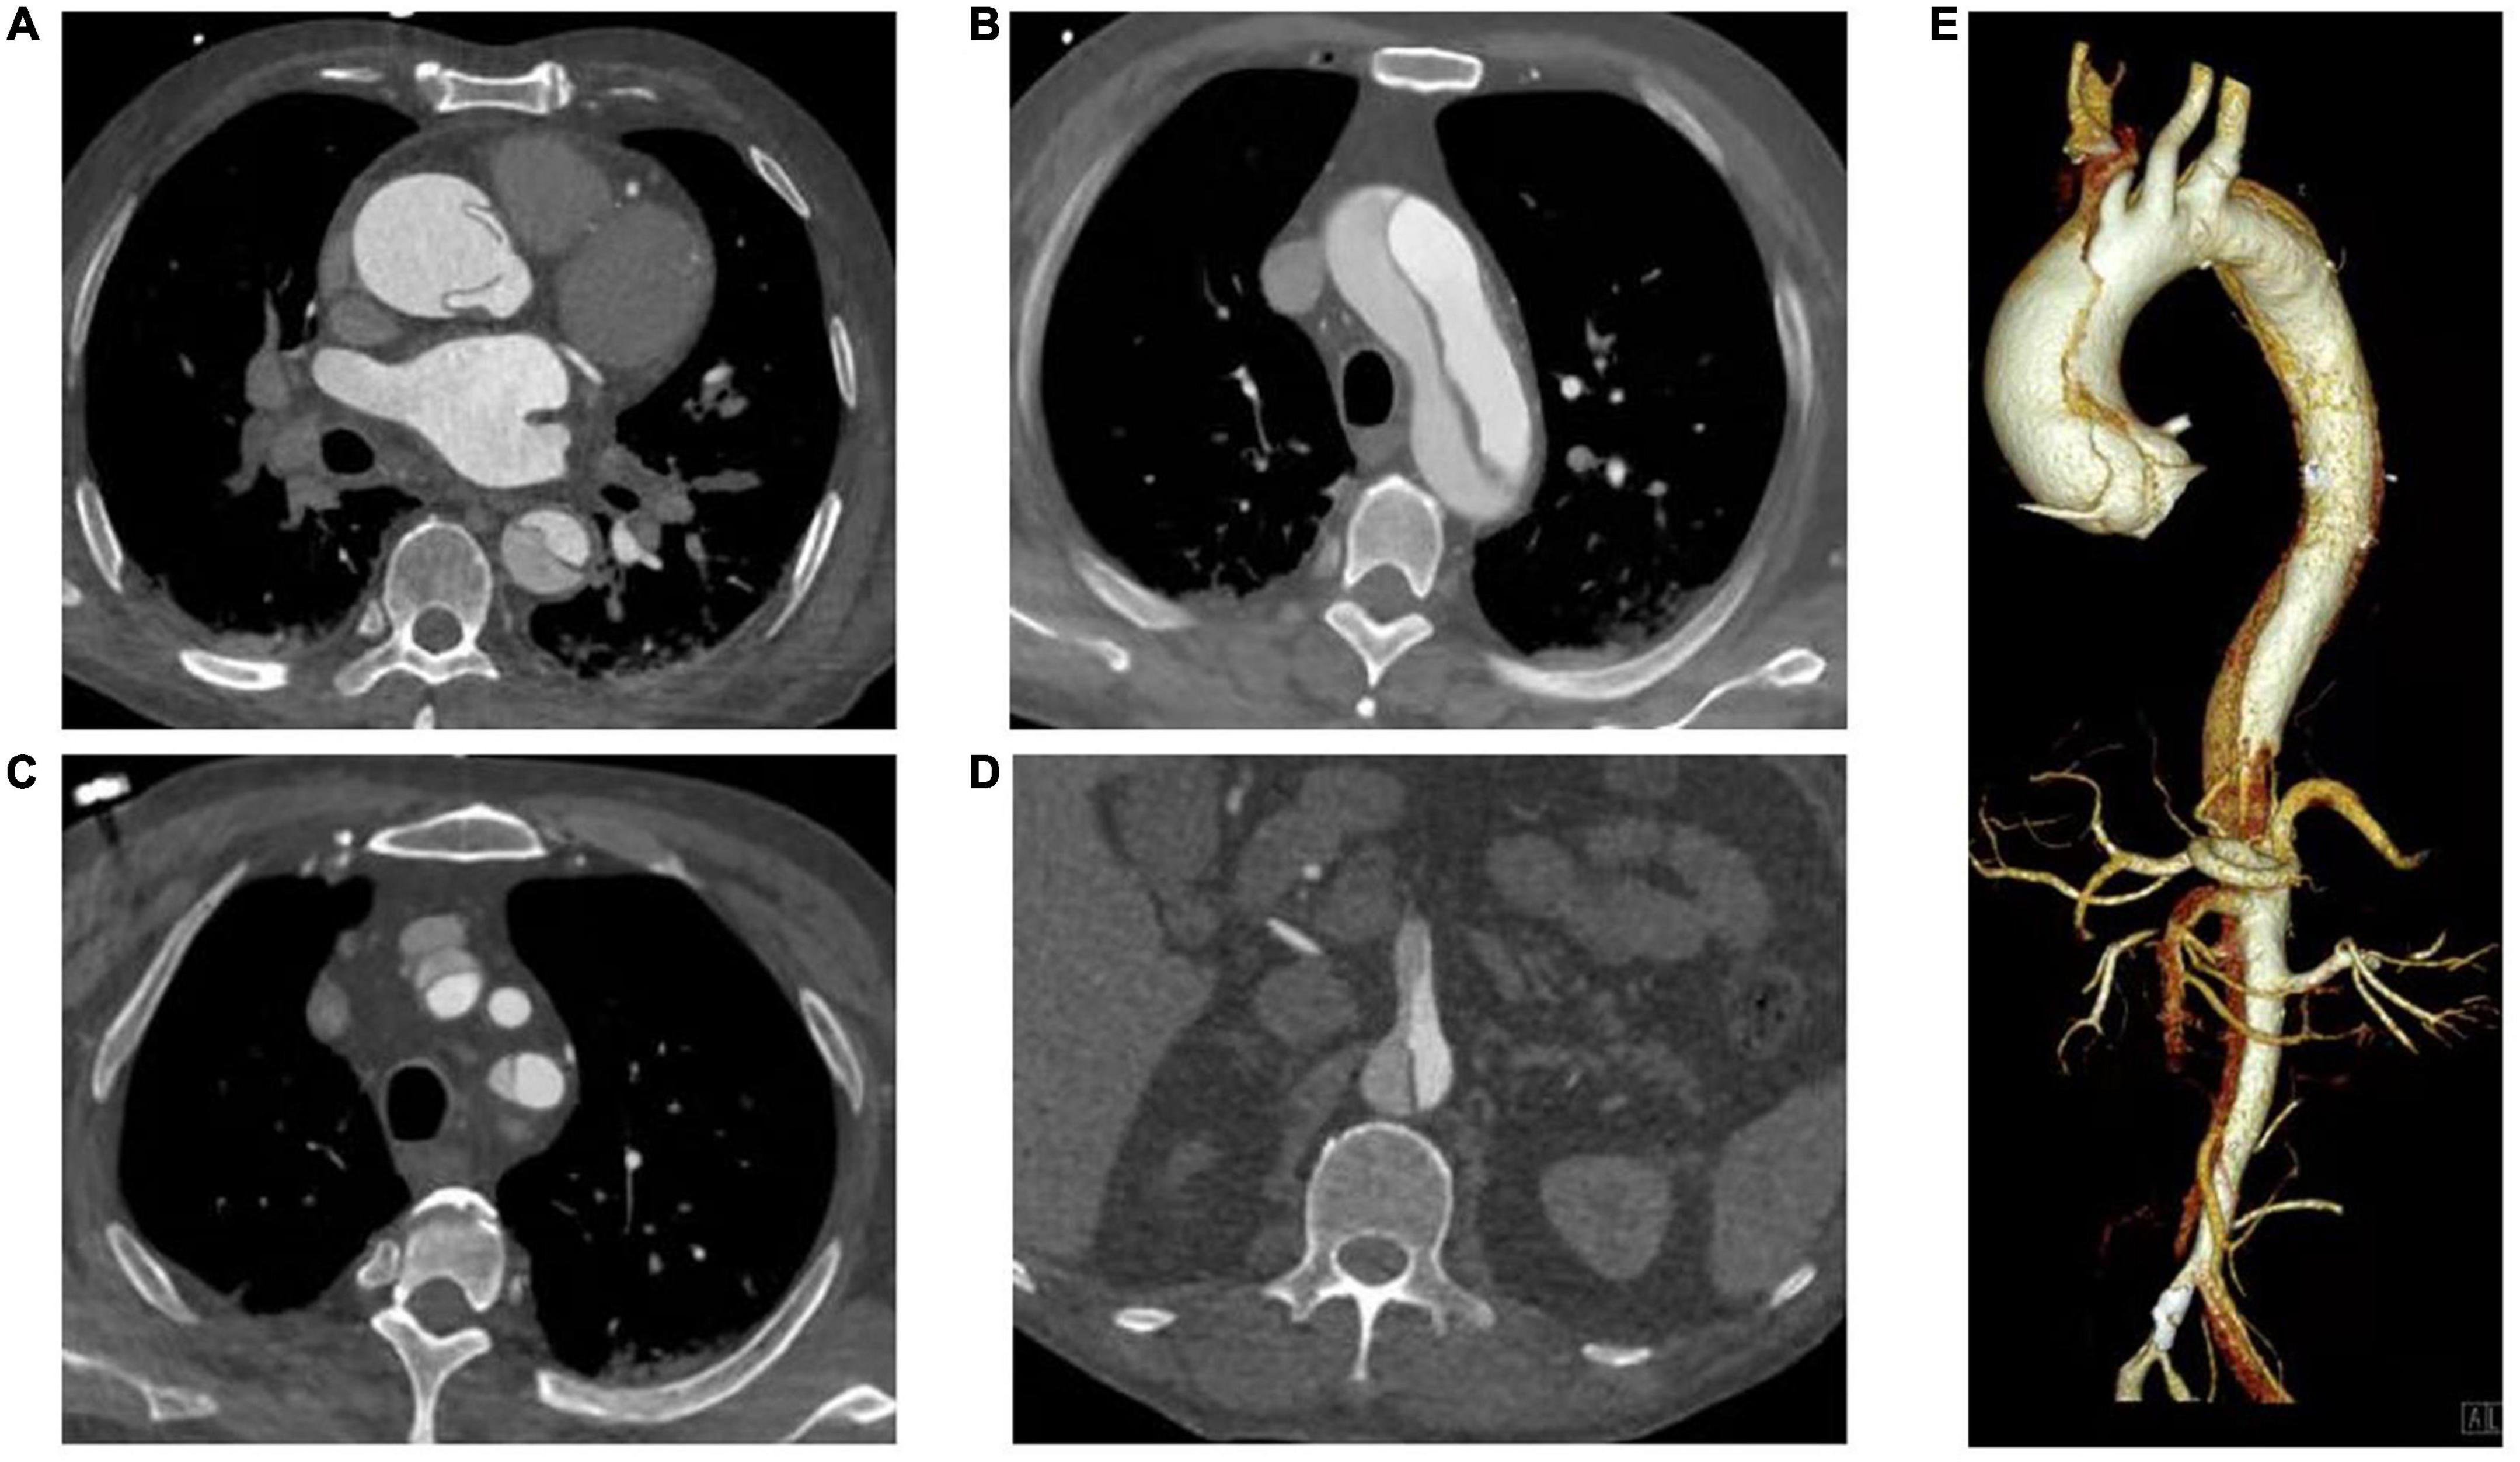

In recent decades, ATAAD has generally been defined as any disease involving the ascending aorta within 14 days after the onset of symptoms (4). Since the time delay from symptom onset to surgical treatment in ATAAD patients significantly changes the survival rate (7), this study selected patients within 7 days of symptom onset according to the new aortic dissection time classification proposed by the IRAD (13). The inclusion criteria were patients aged 18–80 years, diagnosed with ATAAD (CT angiography of the Aorta, Figure 1) and undergoing total aortic arch replacement. The primary exclusion criteria were conservative treatment, death before or during surgery, and symptom onset > 7 days.

Figure 1. CT Angiography of the Aorta. (A) Ascending aorta; (B) Aortic arch; (C) Branch of aortic arch (involving brachiocephalic trunk and left subclavian artery); (D) Aortic dissection involving superior mesenteric artery; (E) Volumetric CT scanning: 3D reconstruction.